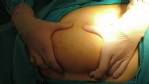

Yapılan operasyon ve hasta hakkında bilgi veren Doç. Dr. Berkan Reşorlu, "Hastamız sol yan ağrısı ve karında şişlik şikayeti ile bize başvuran 62 yaşında bir erkekti. Yaptığımız muayene ve radyolojik görüntülemeler sonucunda sol böbrekten kaynaklanan 20 santim boyutunda bir kitle olduğunu tespit ettik. Bunun üzerine hastayı ameliyata alarak, başarılı bir operasyonla böbrekle birlikte kitleyi çıkardık. Çıkardığımız kitlenin patoloji sonucu sıklıkla kol ve bacaktaki yumuşak dokulardan kaynaklanan ’miksofibrosarkom’ dediğimiz kötü huylu bir tümör olarak geldi. Böyle bir tümörün böbrekten kaynaklanmasını beklemiyorduk. Literatürü araştırdığımızda böbrekten kaynaklanan tek ’miksofibrosarkom’ vakasının 2015 yılında İspanya’dan bildirildiğini gördük. Bunun üzerine bizde olgumuzu hızlı bir şekilde ürolojinin prestijli dergilerinden birinde yayınlattık ve dünyada görülen ikinci vaka olarak literatüre kazandırdık. Hastamızın kitlesi oldukça büyük, çevre organlara yapışık ve ana damarları tamamen sarmış durumdaydı. Oldukça riskli ve zor bir ameliyatın ardından bu kitleyi çıkartarak kemoterapi tedavisine başladık ve şu an hastamızı yakın takip altında tutuyoruz. Böbrek tümörleri, ürolojide prostat ve mesane kanserlerinin ardından en sık izlenen 3. kanser türü ve son yıllarda görülme sıklığı tüm dünyada artıyor. Tüm kanserlerde olduğu gibi bunlarda da erken tanı oldukça önemli. Ancak bu kanser türü sıklıkla tesadüfen saptanıyor. Çünkü hastaların ancak yüzde 10-15’lik kısmında idrardan kan gelmesi, karında şişlik ya da yan ağrısı gibi şikayetlere yol açıyor. Kendilerinde bu tip belirtiler izleyen hastaların vakit kaybetmeden bir üroloji uzmanına başvurmasını öneriyoruz" dedi.

Hastadan çıkarılan kitlenin oldukça büyük, çevre organ ve dokulara yapışık ve ana damarları tamamen sarmış olduğunu belirten Dr. Reşorlu, daha önce de bu tip kitleleri çıkardıklarını ancak patoloji sonucunun miksofibrosarkom olarak gelmesinin kendilerini de oldukça şaşırttığını sözlerine ekledi.